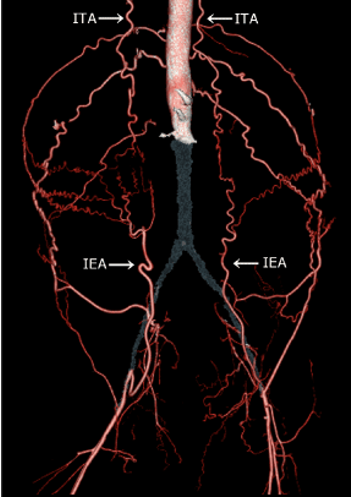

LeRiche’s Syndrome:

occlusion of the abdo aorta that also involves the iliac bifurcation

collateralization to the leg is through epigastric vessels

may see tardus parvus waveforms in femoral arteries